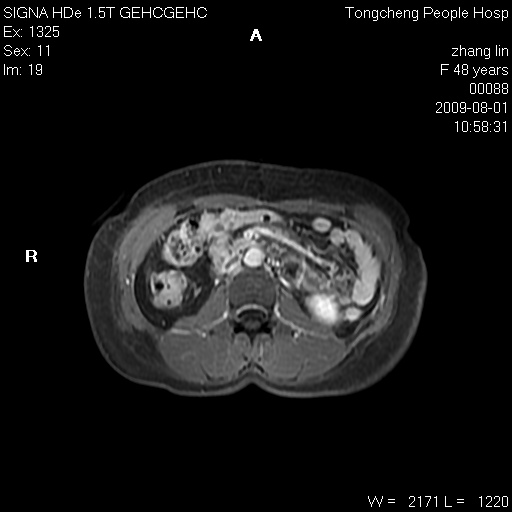

女,48岁。健康体检,彩超发现右肾占位性病变。平素健康。

临床诊断:右肾占位性病变,性质待定(囊肿?肿瘤?)。

上中腹部mr平扫+增强扫描,图像如下:

右肾上极见一类圆形病灶,t1wi呈等信号t2wi呈等高混杂信号,三期增强无强化,边界清---考虑囊肿出血。

同反相位均表现为等信号,病变无强化,考虑含蛋白的囊肿可能,弥散加权相或许有些帮助,